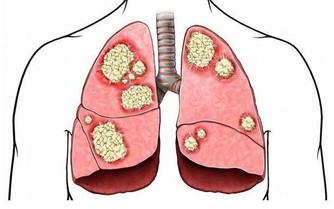

徵兆二:喘不上氣

有些心髒病患者除了常見的症狀外,還會出現呼吸急促、喘不過氣來的現象,這種呼吸困難常被人們稱為氣不夠用。

這種喘息常常被人忽視,尤其是患有肺病老年人,更易被忽視。